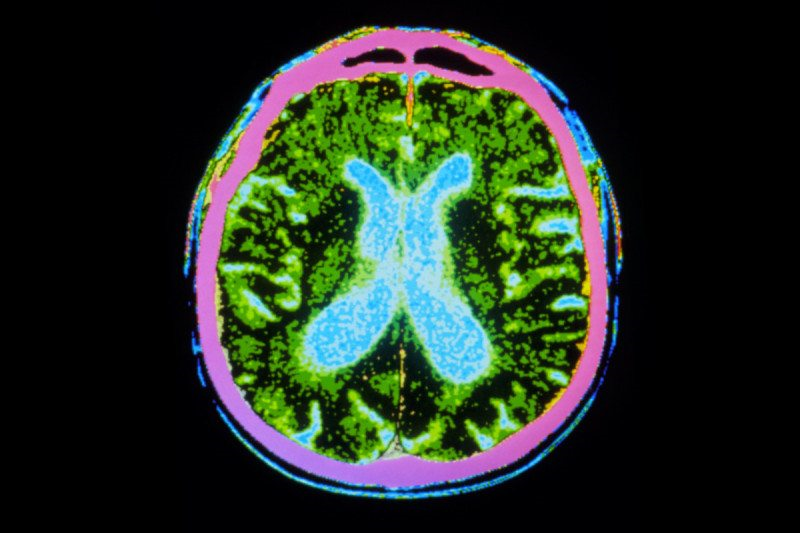

帕金森是由于多巴胺能细胞逐渐丧失所致。多巴胺是一种化学性神经递质,它主要协助控制运动。目前帕金森主要采用药物替代疗法,但是今年来替代药物的药效性正在降低。

新西兰奥克兰市正在研究一种活体细胞抑制技术。采用猪的脉络丛细胞治疗帕金森病。这些组织可以产生一系列的生长因子和分子信号有助于神经细胞的健康。

上个月,他们进一步做了安慰剂对照实验,移植了18例患者。他们希望这种方法可以滋养帕金森病人幸存的多巴胺能神经元,减缓神经细胞的进一步丢失。

这种技术在帕金森大鼠身上已经成功。“通过植入这种神经化学物质工厂可以显著改善新的神经细胞的生长和修复”。活体细胞技术专家肯.泰勒说。